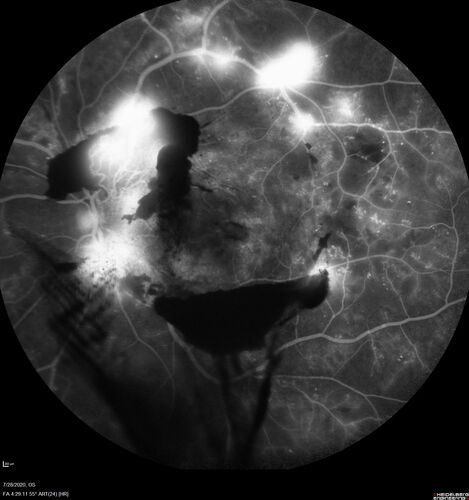

Proliferative Diabetic Retinopathy and vitreous hemorrhage left eye

44 year old man with type II diabetes for 14 years and no eye examinations in the last 5 years.  VA 20/40 right eye and 20/60 left eye.  Vision loss has been for about a week in the left eye.